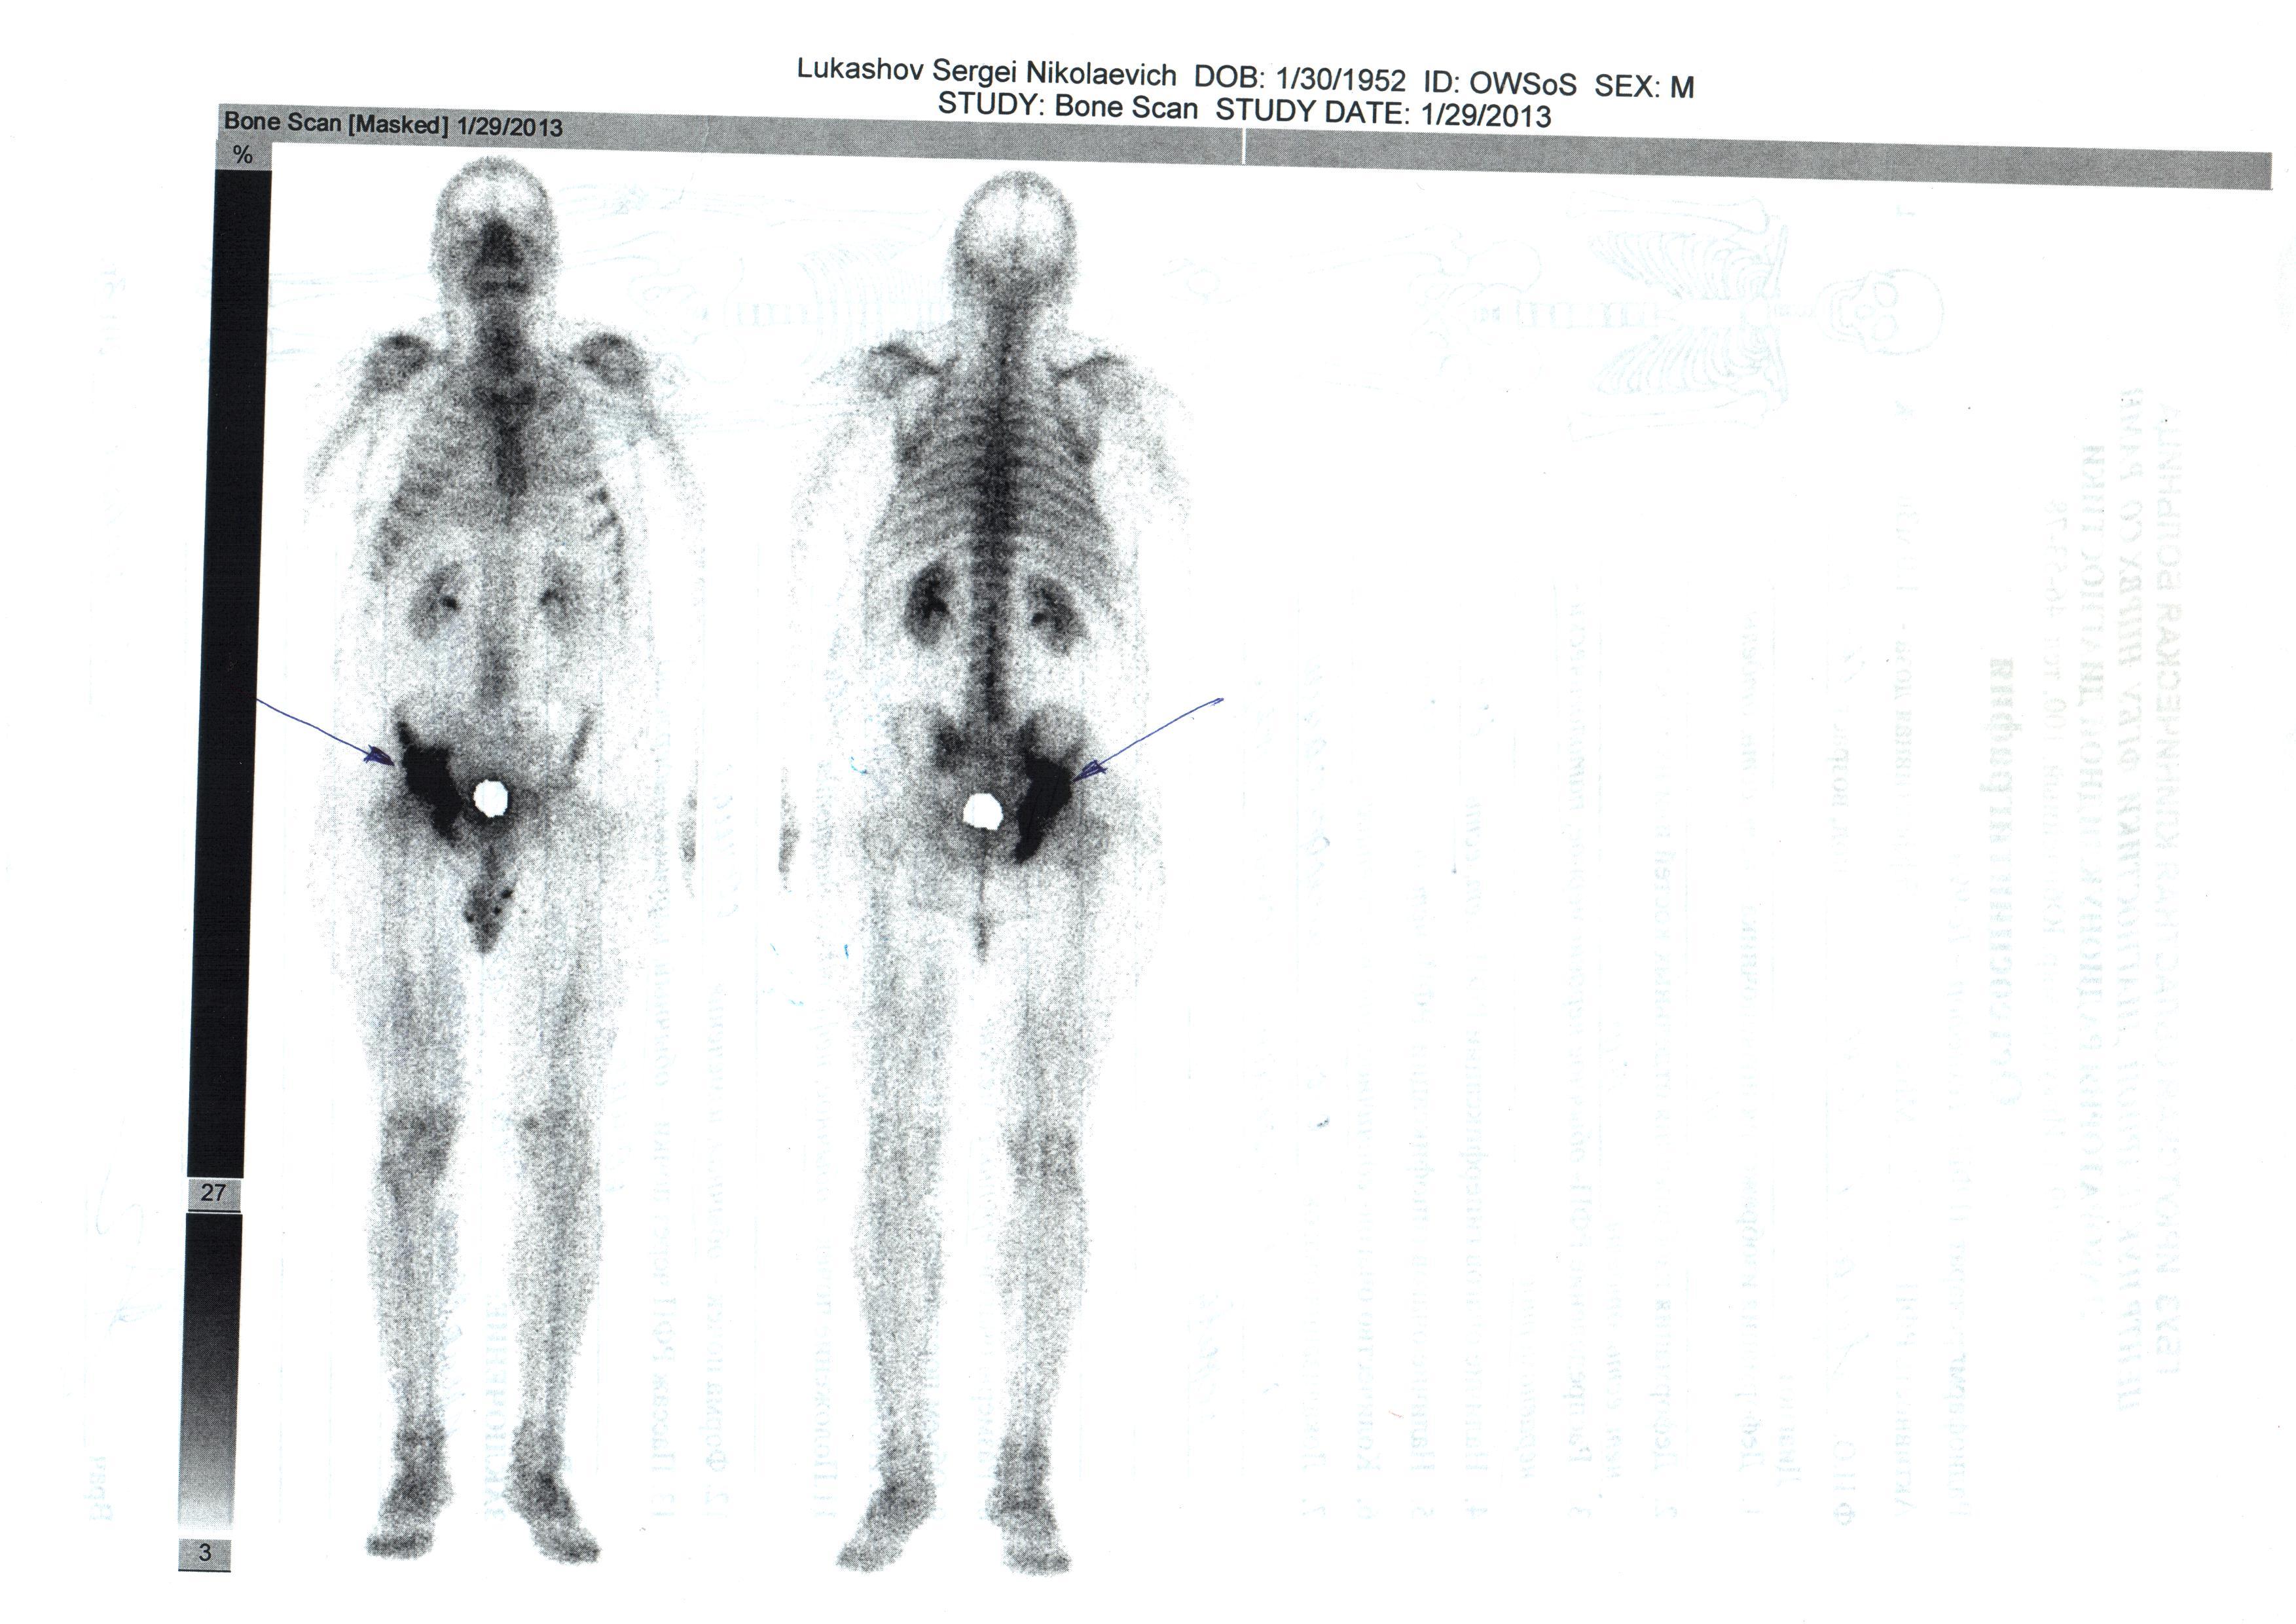

29.01.13 0стеосцинтиграфия:очаг гиперфиксации в костях таза справа.

Дз: Рак предстательной железы "T2N0M0 II ст 4 кл.гр.Метастазы в кости.